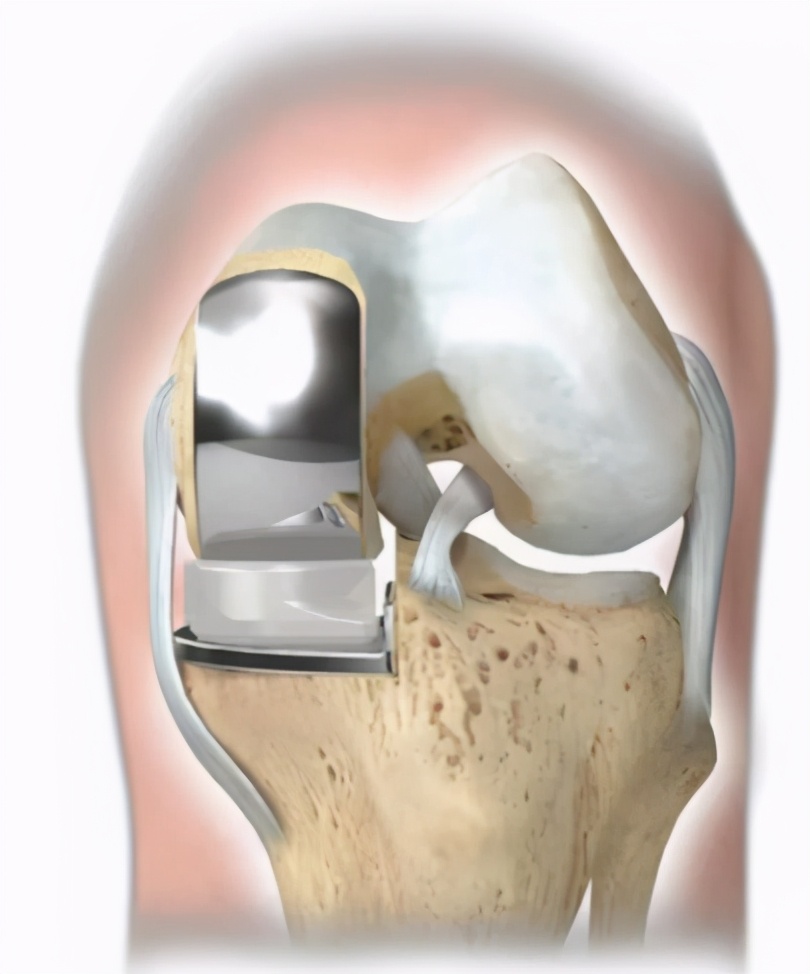

如果把膝关节比作房屋,那么人的膝关节共有3个房间,分别是内侧间室、外侧间室和髌股间室。膝关节单髁置换术针对的是膝关节单间室骨关节炎病患,如内侧或外侧间室,保留全部的韧带组织和其余间室关节软骨,从而实现术后的快速康复。